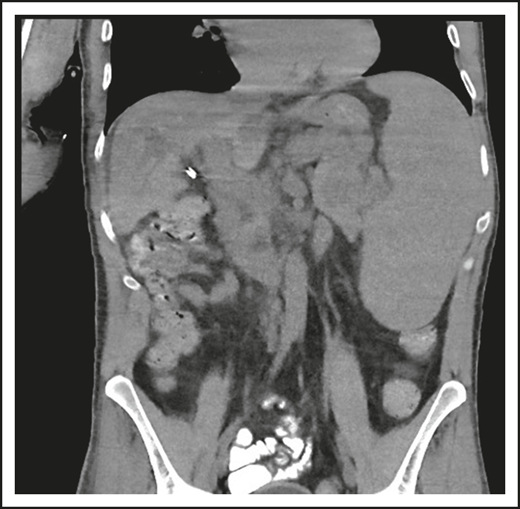

A second common reason for a patient to come to the attention of hematologists is the finding of an enlarged spleen, especially in an adult with lymphadenopathy. This was the reason in patient 2, who is now a 46-year-old male professional dog walker. At the age of 31, he was found to have an enlarged spleen together with cervical and axillary lymphadenopathy. Hematology was consulted, and the lymph node was biopsied; pathology revealed that he had noncaseating granuloma. He was then referred to pulmonology and, with this evidence, was diagnosed with sarcoidosis and treated with steroids for some months, but he stopped the treatment. Although he had no obvious respiratory symptoms over the following 15 years, he had a slow decline in lung function, and chest computed tomography showed hilar lymphadenopathy, ground-glass opacities with nodules, and bronchiectatic changes (Figure 2). In 2018, he had acute bacterial pneumonia, became concerned, and found on the internet that granulomata in the lungs and an enlarged spleen might be related to low serum immunoglobulin levels. He asked that this be tested; when this test was performed, he had striking low serum immunoglobulins: IgG, 97 mg/dL; IgA, <5 mg/dL; IgM, 27 mg/dL. However, within the month, he was hospitalized for pneumonia due to metapneumovirus. The diagnosis of CVID was finally made, and immunoglobulin treatment was started. The patient’s spleen remains large.

The patient in clinical case 2 had a slow decline in lung function due to his immune defect, but this was assumed to be due to sarcoidosis. Chest computed tomography showed ground-glass opacities with numerous nodules, hilar lymphadenopathy, and bronchiectatic changes. With granuloma on biopsy, these changes were consistent with granulomatous lymphocytic interstitial lung disease.

Granuloma in tissues

Localized or systemic granulomatous disease, sometimes erroneously called “sarcoidosis,” occurs in between 8% and 22% of subjects with CVID.18,19 For unclear reasons, many of these patients have also had ITP or AIHA. In the patient in clinical case 2, although he did not have characteristic lung infections such as pneumonia for many years, the diagnosis of “sarcoid” retarded the recognition of the underlying immune defect; this confusion has repeatedly been observed, and the delay in diagnosis can be for more than a decade, as it was in this case.19 Organisms must be sought but are very rarely found. In CVID, the granulomatous changes are usually found in lungs, lymph nodes, or spleen, but the skin, liver, bone marrow, kidney, gastrointestinal tract, and brain can also be involved. In the lungs, an intense lymphoid infiltration accompanies the granulomas, leading to what is termed “granulomatous lymphocytic interstitial lung disease.”18 For unclear reasons, patients with granulomatous disease are likelier to have ITP or AIHA than those with CVID, who do not have this pathology and thus require the attention of hematologists.